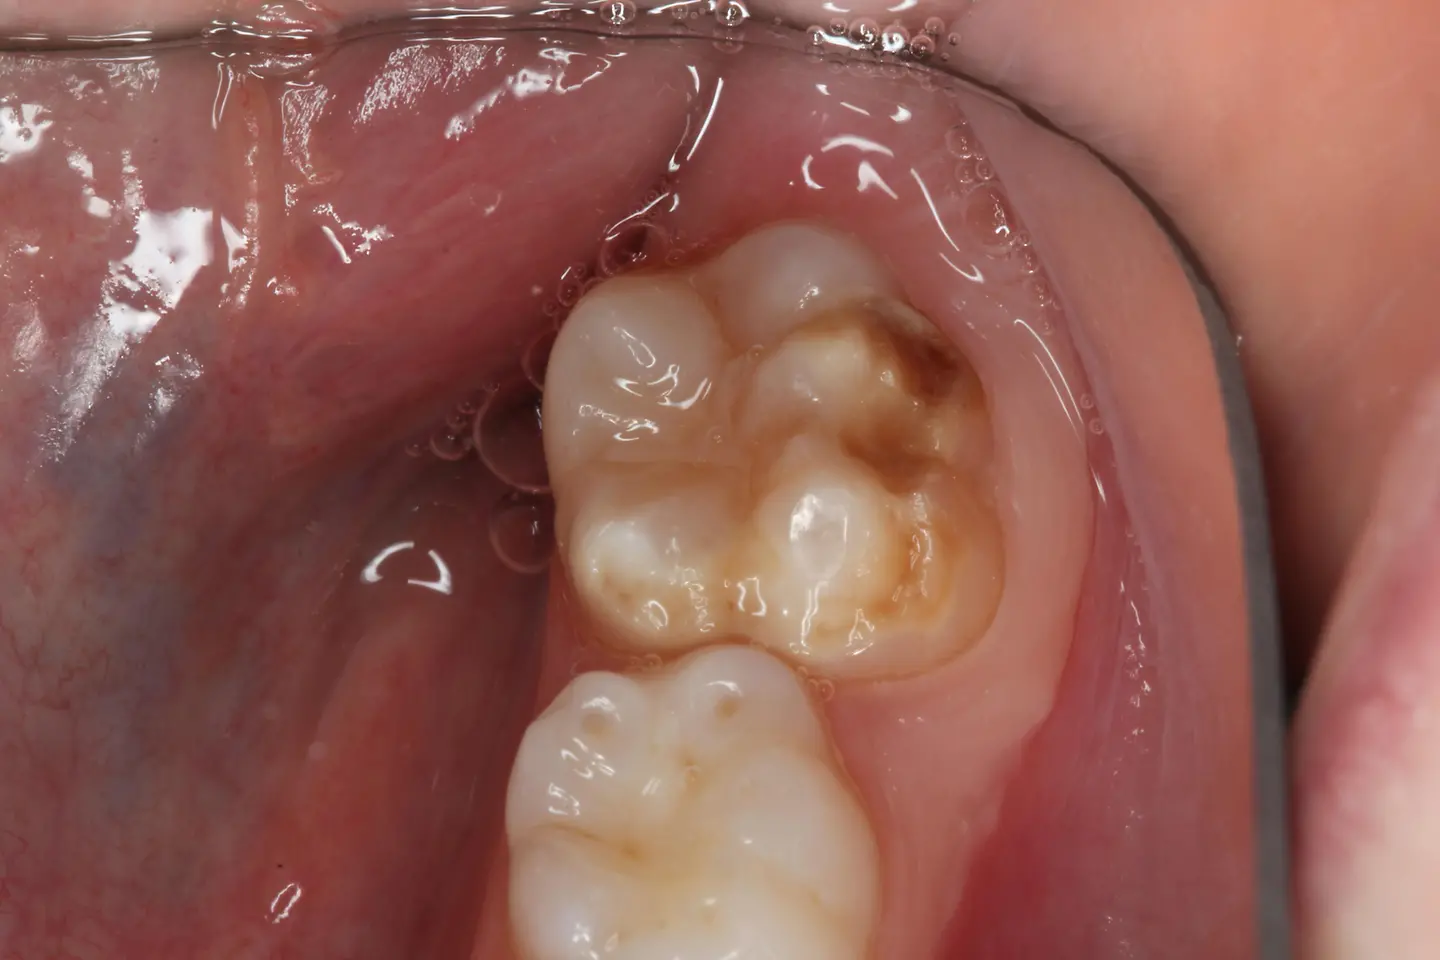

Es gibt Erkrankungen, die Ärzten und Wissenschaftlern Rätsel aufgeben. Zu diesen Krankheitsbildern zählen die sogenannten „Kreidezähne“, medizinisch „Molaren-Inzisiven-Hypomineralisation (MIH). Die Schmelzbildungsstörung tritt meist an den ersten bleibenden Backenzähnen auf, häufig auch an den bleibenden Frontzähnen. Untersuchungen zeigen: Auch Milchzähne können schon betroffen sein. Die Zähne haben weiße bis gelblich-braune Flecken – je größer und dunkler die verfärbten Stellen sind, desto stärker ist die Mineralisationsstörung.

Blick in einen Kindermund mit Zähnen, die eine moderate Form der MIH aufweisen

Moderate Form der MIH, gemeinhin als Kreidezahn bezeichnet. Foto: Prof. Dr. Dr. Norbert Krämer